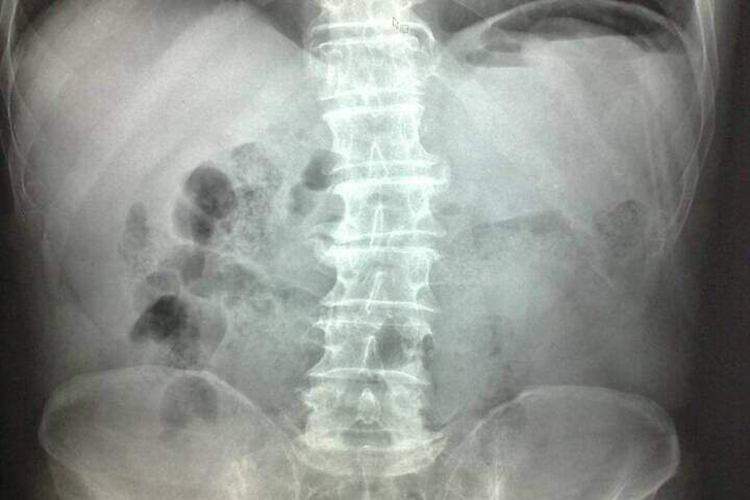

胃肠穿孔X线表现为立位时可见膈下游离气体的气腹征象,多伴腹痛、板状腹等症状。

胃肠穿孔X线表现为立位时可见膈下游离气体的气腹征象,或用胃管抽空胃液后注入空气300ml,空气可自穿孔处逸出形成膈下气影,多伴腹痛、板状腹等症状。